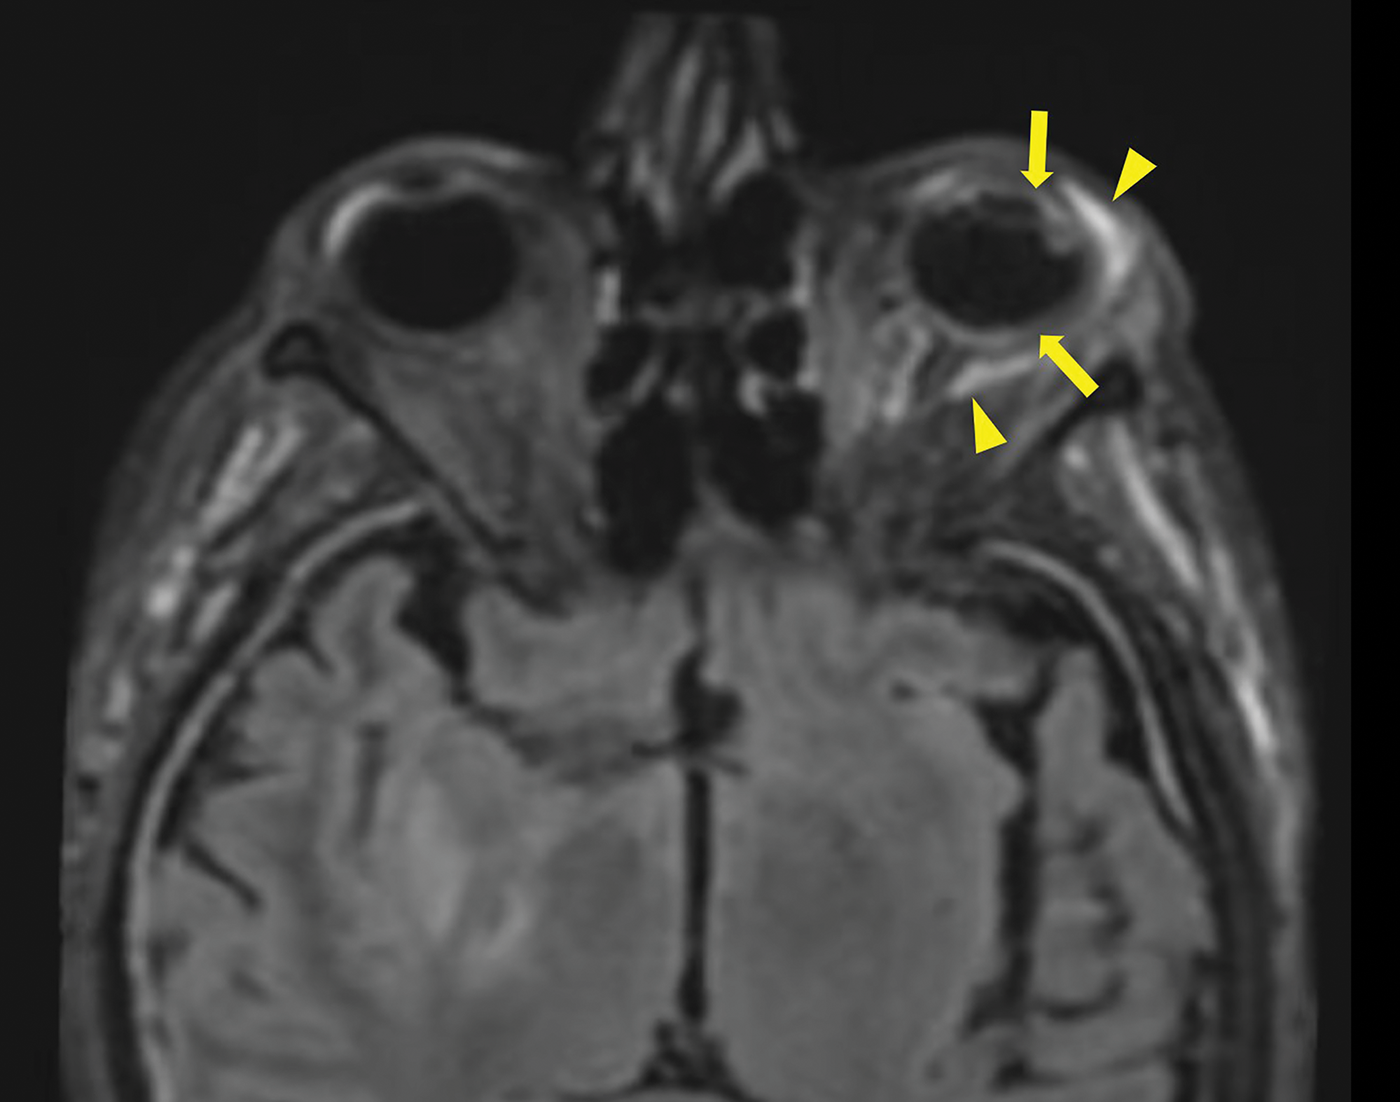

After ruling out cavernous sinus thrombosis with a contrast‑enhanced CT scan, a brain MRI was performed, confirming the diagnosis of endophthalmitis. MRI showed pre‑septal orbital cellulitis, with pre‑septal enhancement seen on the 3D T1 Dixon sequence (Figure 1, arrowhead). This was associated with increased scleral enhancement and alterations at the junction between the left ocular globe and the optic nerve (Figure 1, arrow). Of note also the slight increase in T1 signal of the vitreous body (Figure 1, star). There was choroidal and peri‑septal inflammation with fat saturation after contrast injection, and in the 3D FLAIR sequence, showing a pre‑septal and peri‑optic hypersignal (Figure 2, arrowheads). Additionally, there was an increased signal in the choroid and ciliary body, as well as thickened dura mater, in relation to the meningitis (Figure 2). Axial T2 gradient echo sequences showed retinal detachment and inflammation around the distal portion of the optic nerve, with a slight linear hypoT2 signal (Figure 3, arrow).

Figure 2

3D FLAIR Sequence with Fat saturation post contrast injection showing a pre‑septal and a perioptic hypersignal (arrowheads), a increase signal of the choroid and of the ciliary body. Also note the thickened dura mater in relation to the meningitis.